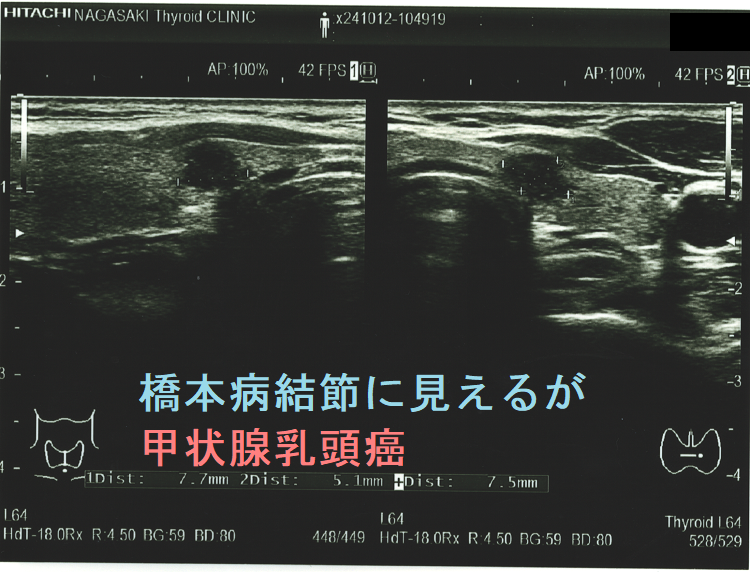

ケース① どう見ても腺腫様結節、しかし甲状腺乳頭癌